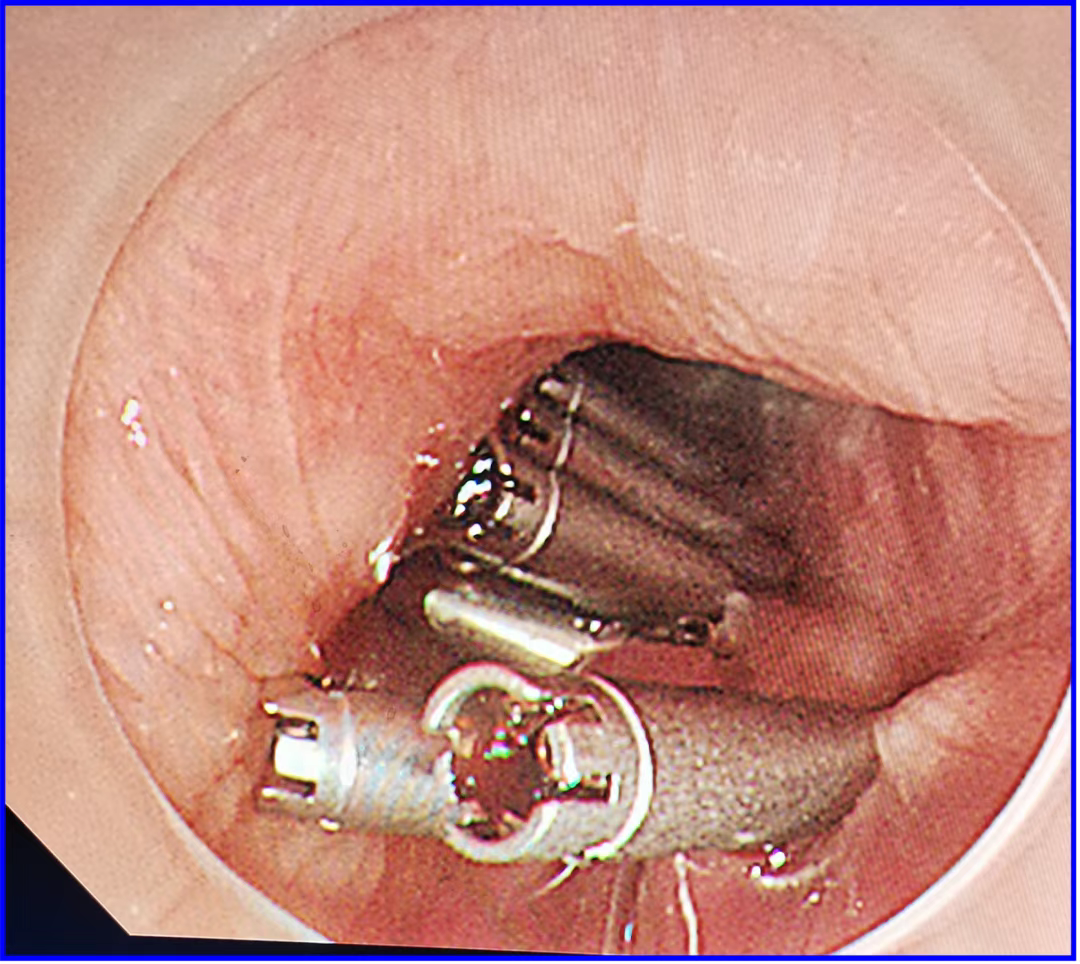

巨大胆管结石克星之---Spyglass

ERCP是内镜微创治疗技术的典范代表。近年spyglass的出现是一个亮点,其可在直视下进行胆胰管内活检甚至碎石治疗,突破了原内镜治疗的盲区,ERCP又焕发了新的可能。今年,我院率先引进了河西地区第一台(胆道镜)spyglass 为当地区胆管结石患者带来了福音。患者宋某于入院数3年前因腹痛就诊当地医院完善相关检查诊断胆管结石伴有胆管炎,因患者胆管多发并且结石大于1.0cm,ERCP球囊及网篮取石困难而无法取出,后多次就诊我科行ERCP及胆管支架置入。2023年3月该患者再次并发胆管炎而就诊我科。十二指肠乳头处可见支架一枚,切开型乳头,拔除支架。插管成功后,造影示胆总管扩张,其内见数个充盈缺损影,最大约1.2x1.0cm大小。Spy-Glsss见胆总管褐色结石,碎石后,引入直径1.4cm扩张球囊扩张乳头口,扩张成功后以取石球囊分次取出数块褐色结石数枚,另分次取出大量泥沙样结石,过程顺利。